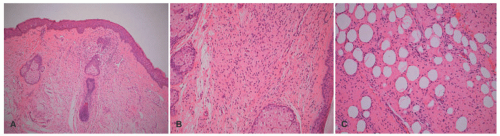

The histopathologic features of DF are relatively uniform in the majority of cases as a dermal-based spindle cell proliferation positioned in the mid-dermis, situated beneath the flattened epidermis or pushing into the underlying subcutis with absent or minimal infiltration into the subcutis, unlike the DFSP (Figure 24-31A-C). The lateral dermal borders typically demonstrate the spindle cells extending into the collagen with so-called collagen trapping. Within the body of the lesion, the spindle cells are arranged in short storiform or fascicular profiles. Some nuclear pleomorphism may be present together with scattered mitotic figures. Lymphocytes and even eosinophils may be identified in the background. Variant patterns include those with blood-filled nonvascular spaces (aneurysmal DF), numerous macrophages with hemosiderin-laden cytoplasm, and xanthomatized macrophages. Touton giant cells in the latter setting presents the microscopic dilemma and distinction (if there is one) from the xanthogranuloma (Figure 24-32). More than one histologic pattern is present in a minority of DFs.141

FIGURE 24-31. A-C, Dermatofibroma presenting on the breast of a 17-year-old female. A, The spindle cell tumor is centered in the dermis as a circumscribed nodule. Mild acanthosis noted in the overlying epidermis. B, This focus shows the uniform spindle cells arranged in a storiform profile. C, The periphery demonstrates the insinuation of spindle cells into adjacent dermis with collagen trapping. Note the limited extension.